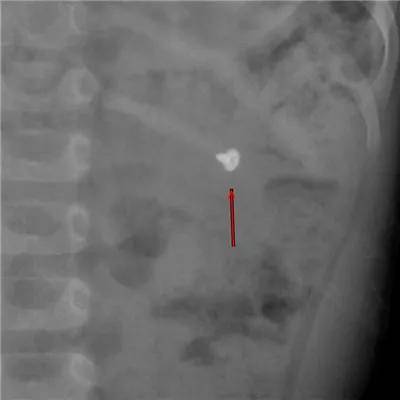

各种年龄误服螺丝钉

这是误服的几个钝头钉,危害相对较小,但看着也很吓人。